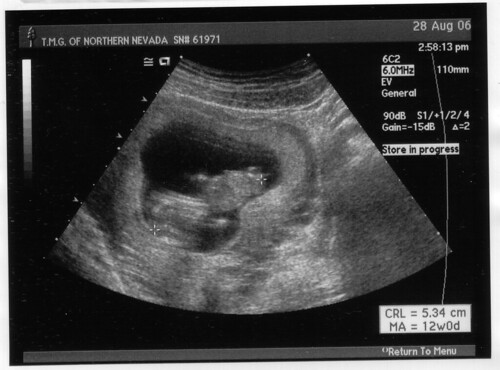

Exciting news! Adrienne is resting and I hold in my arms (typing this with one hand): Liam Alexander Cole, born on Friday, March 2nd at 15:31 PST (GMT-0800). He weighs 7 lbs 11.5 oz (3501 g) and is 18.75 inches (47.6 cm) long/tall.